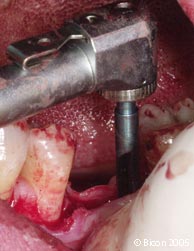

用2.0mm的先锋钻在1100RPM的转速下预备牙槽骨,同时需要外部冲水降温。 |

![]() |